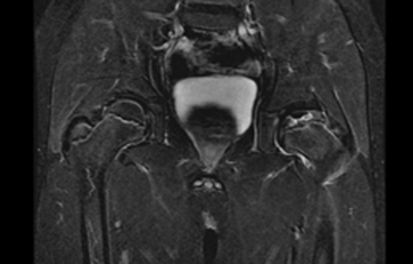

Post-Processing: Perform manual subtractions of the coronal and sagittal T1 Fat Sat sequences – postcontrast – precontrast = subtracted image. It should look like this: